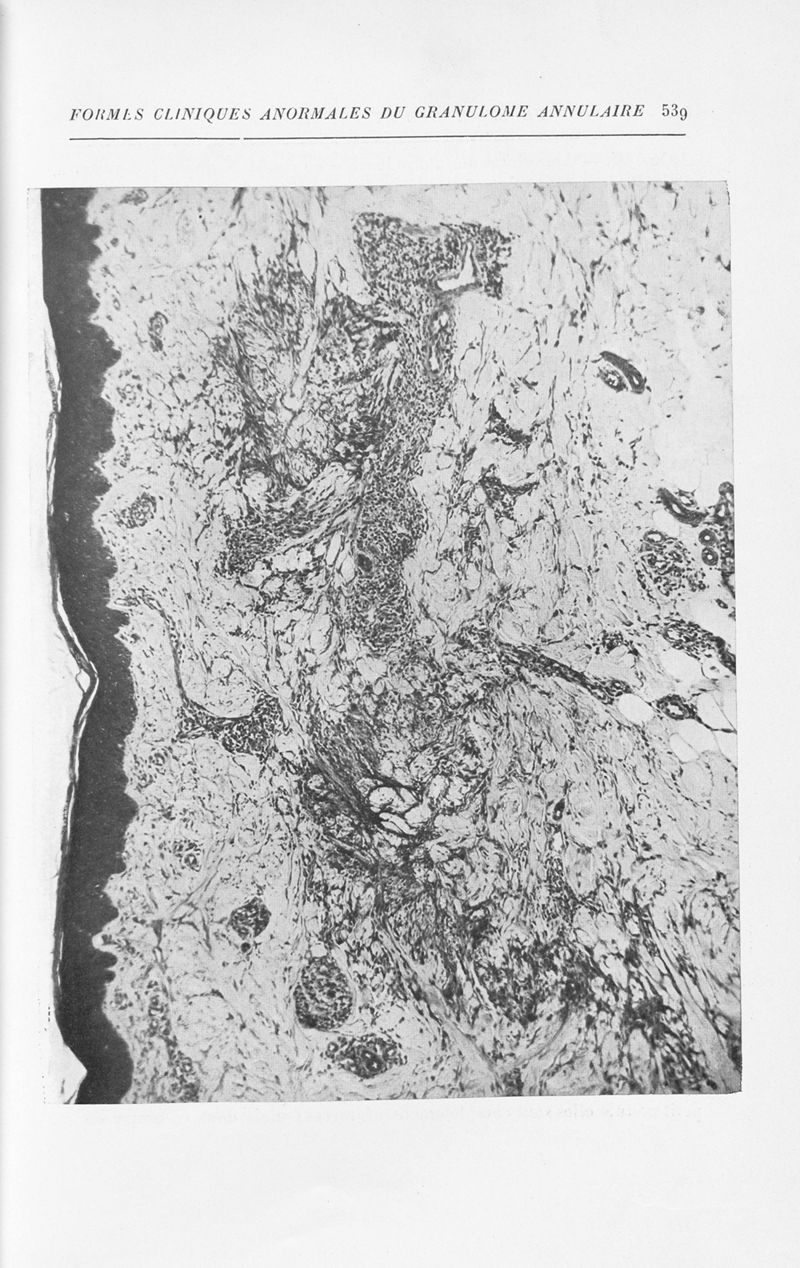

Annales de dermatologie et de syphiligraphie

7ème série, tome VIII. - Paris : Masson, 1937.